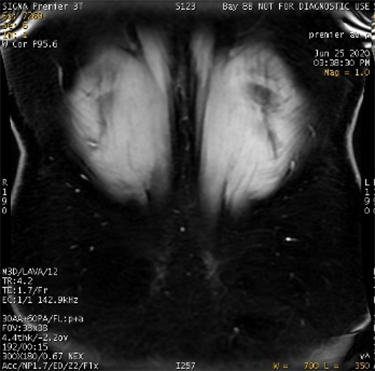

| Fat/Water Swap Areas that should appear fat suppressed are water suppressed, and ar-eas that should appear water suppressed are fat suppressed | ![]()

| Decreased linearity at the corners of the FOV corrupt the signal. The fat water identification algorithm may become confused, which results in a full series fat/water image swap. Phase wrap in slice and phase direction also influence swaps. This error may occur in regions of high magnetic field variation, in spatially isolated tissue, and/or in images with low signal-to-noise ratios, due to: